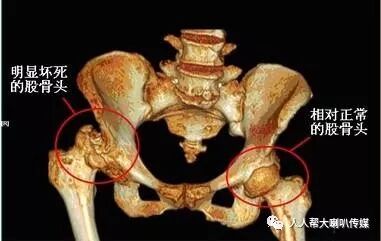

股骨头缺血性坏死,又称股骨头无菌性坏死、股骨头软骨炎、股骨头扁平症。多见于5-14岁的男童,或者30-50岁女性。引起本病的原因有:外伤后供血障碍;轻度感染致使供血障碍或骨骺生长过快;过敏反应或缺乏维生素所致。

中医认为股骨头受伤,由于病人肝肾亏虚,则筋骨失养,故见骨质坏疽,筋骨枯萎,屈伸不利。